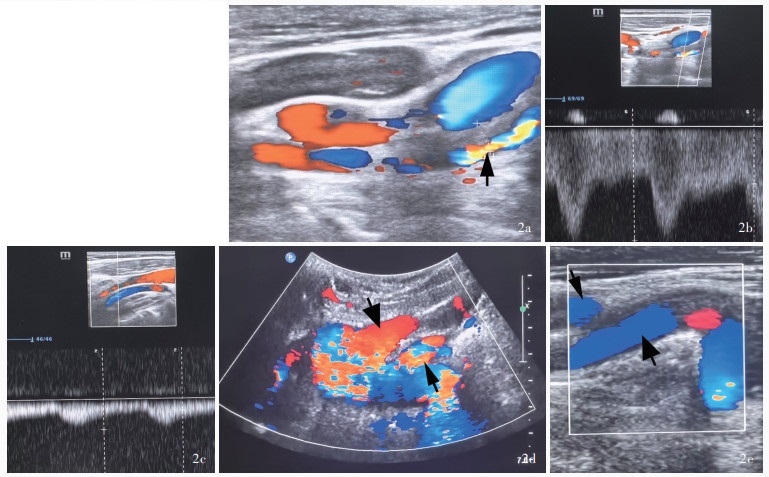

Zhao XY , Tang HX , Jing XX , Zhang J . Imaging manifestations of congenital absence of internal carotid artery: a case report. Lin Chuang Chao Sheng Yi Xue Za Zhi, 2024, 26: 453.

|

赵晓艳, 唐海霞, 景香香, 张洁. 先天性颈内动脉缺如影像学表现1例. 临床超声医学杂志, 2024, 26: 453.